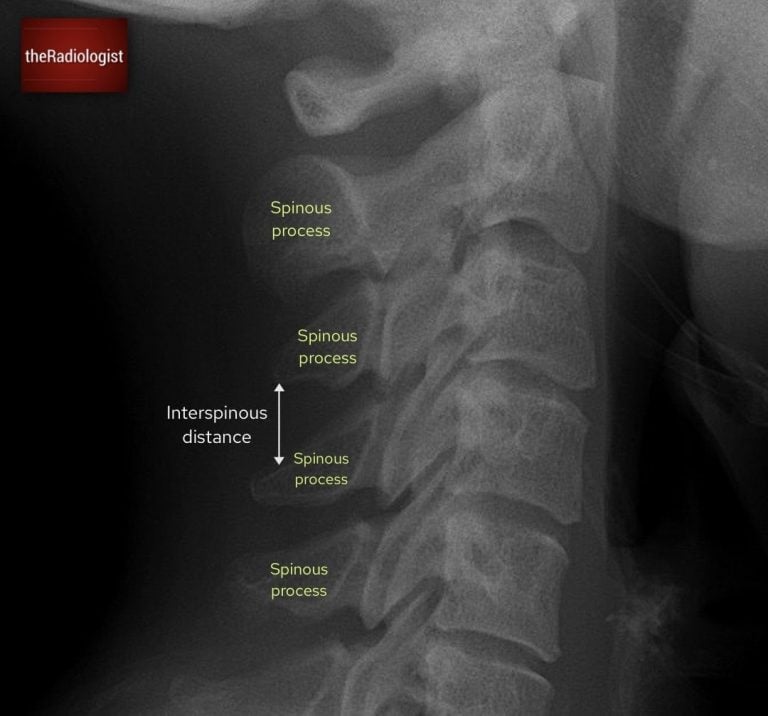

6. Spinous processes and interspinous distance

The spinous processes should be traced in sequence from C2 to C7. Each should be aligned in a straight line, with relatively uniform spacing. A focal increase in the interspinous distance indicates potential disruption of the posterior ligamentous complex and anterior cervical dislocation. Careful assessment of these intervals is particularly important in flexion-type injuries.

Look at the spinous processes and ensure the interspinous distance is relatively similar: more than 1.5 times difference can be significant